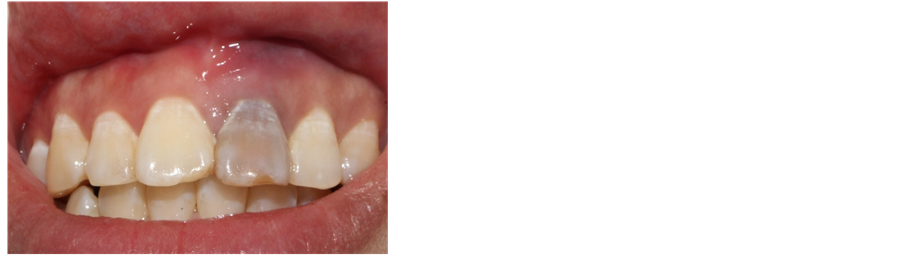

A 28-year-old female patient was treated in Department of Stomatology, Fujian Medical University Union Hospital on March 11th 2016 with chief complaint of “gingiva of the left upper anterior tooth suppurated for one month”. A decade ago, the patient had tooth trauma. One year ago, the patient had root canal therapy in other hospital for the 21st tooth. One month ago, the patient was treated in our hospital for repeated suppuration at gingiva of the 21st tooth. The patient is healthy in the past, denying systematic disease, infectious disease, drug allergy history, poisoning history and trauma history in last ten years. Clinical para-oral examination (Figures 1-2): The maxillofacial region is basically symmetrical in left and right; no tenderness in temporal-mandibular joint and no click and fricative when opening and closing mouth; parotid gland is normal in palpation; no swelling in lymph gland. Intraoral examination: there is tooth stain and fistula at gingiva in the 21st tooth, the crown is dark and 21 (++) is not loose, the teeth of the teeth were normal and the 11 teeth were cut by 1/3. X-ray periapical film shows (Figure 3): 21st tooth is low-density shadow under large-area and high-density projection at apex with defective root filling. The patient wanted to improve the tooth color without wearing too much tooth when solving the suppuration at apex.

Figure 1. Discoloration of teeth after trauma.